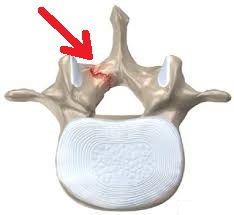

Las fracturas por estrés pueden ocurrir en huesos sometidos a presión constante y repetida, por sobreuso, o micro traumatismos repetidos. Pueden ocurrir en los pies, la rodilla, tibia, peroné, cuello femoral, vértebras, antebrazos etc.

Se puede sospechar el diagnóstico al examinar al paciente y escuchar su historia clínica, Las Rx en algunas ocasiones pueden mostrar la lesión, pero generalmente pasan desapercibidas en los primeros días de los síntomas. La RESONANCIA MAGNÉTICA es el exámen más preciso que puede revelar la lesión y confirmar el diagnóstico que se sospecha.

El tratamiento consiste en reducir o eliminar el peso o tensión que soporta el hueso. Puede ser necesario inmovilizar con yeso o férula, usar muletas o andador, guardar reposo. Cuando fallan los tratamientos iniciales, algunas personas requieren Terapia con Ondas de choque, plasma rico en plaquetas, terapia en cámara hiperbárica, electroestimulación, magnetos, entre otras.

Por tratarse de una fractura, el proceso biológico de consolidación ósea toma de 6 a 12 semanas, dependiendo del hueso afectado. El dolor puede desaparecer en pocos días al iniciar el tratamiento.